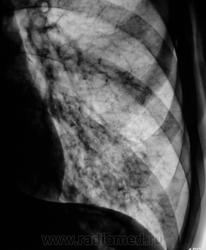

Пациент направлен на рентгенографию ОГК с диагнозом - "Левостороняя пневмония".

Анамнез стандартный. Ранее неоднократно страдал обострениями хронического бронхита. Сейчас вот не нашутку занемог - температура до 38, откашливает мокроту, кашель продуктивный.

Диагноз левосторонней нижнедолевой С10, С9 сементарной пневмонии наверное будет верным, а с учётом фона- с наличием бронхоэктазов.